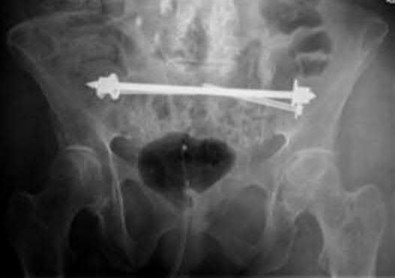

Question 22

During a primary total hip arthroplasty (THA), a multi-hole hemispherical acetabular component is used. The surgeon plans to place adjuvant screws for initial stability. Based on the Wasilewski quadrant system, placing a screw in the anterior-inferior quadrant places which of the following structures at highest risk of injury?

Explanation

According to the Wasilewski quadrant system (divided by a line from the ASIS through the center of the acetabulum and a perpendicular line), the posterior-superior quadrant is the safe zone for screw placement with the best bone stock. The anterior-superior quadrant places the external iliac artery and vein at risk. The anterior-inferior quadrant places the obturator nerve and vessels at risk. The posterior-inferior quadrant places the internal pudendal and inferior gluteal vessels at risk.